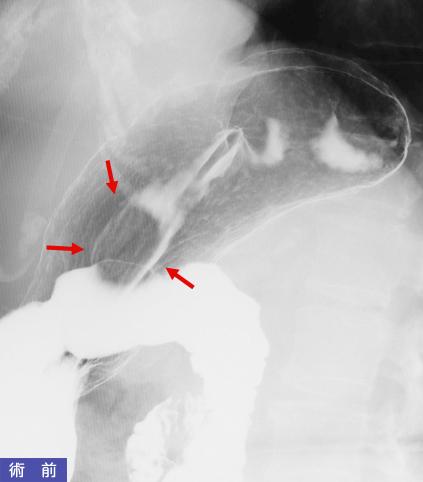

疾患(病理主体)の分類悪性非上皮性腫瘍/平滑筋肉腫(含GIST)

部位(臓器別)胃(部位)/体部

検査方法X-P

病変の最大径(ミリ)25〜29